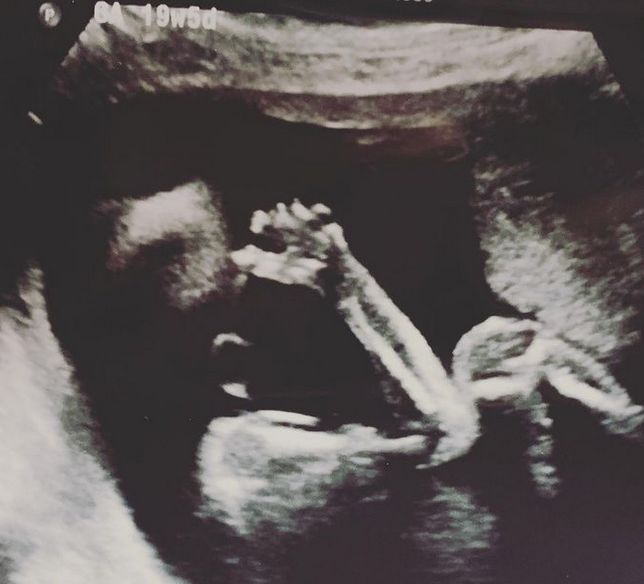

Córka Amy

Córka Amy © Facebook

Siostry dokumentują swoją podróż do macierzyństwa na Instagramie. Wiadomo już, że w październiku na świat przyjdzie dziewczynka. Kobiety planują również, że zarówno Amy, jak i Anthony będą obecni podczas porodu.